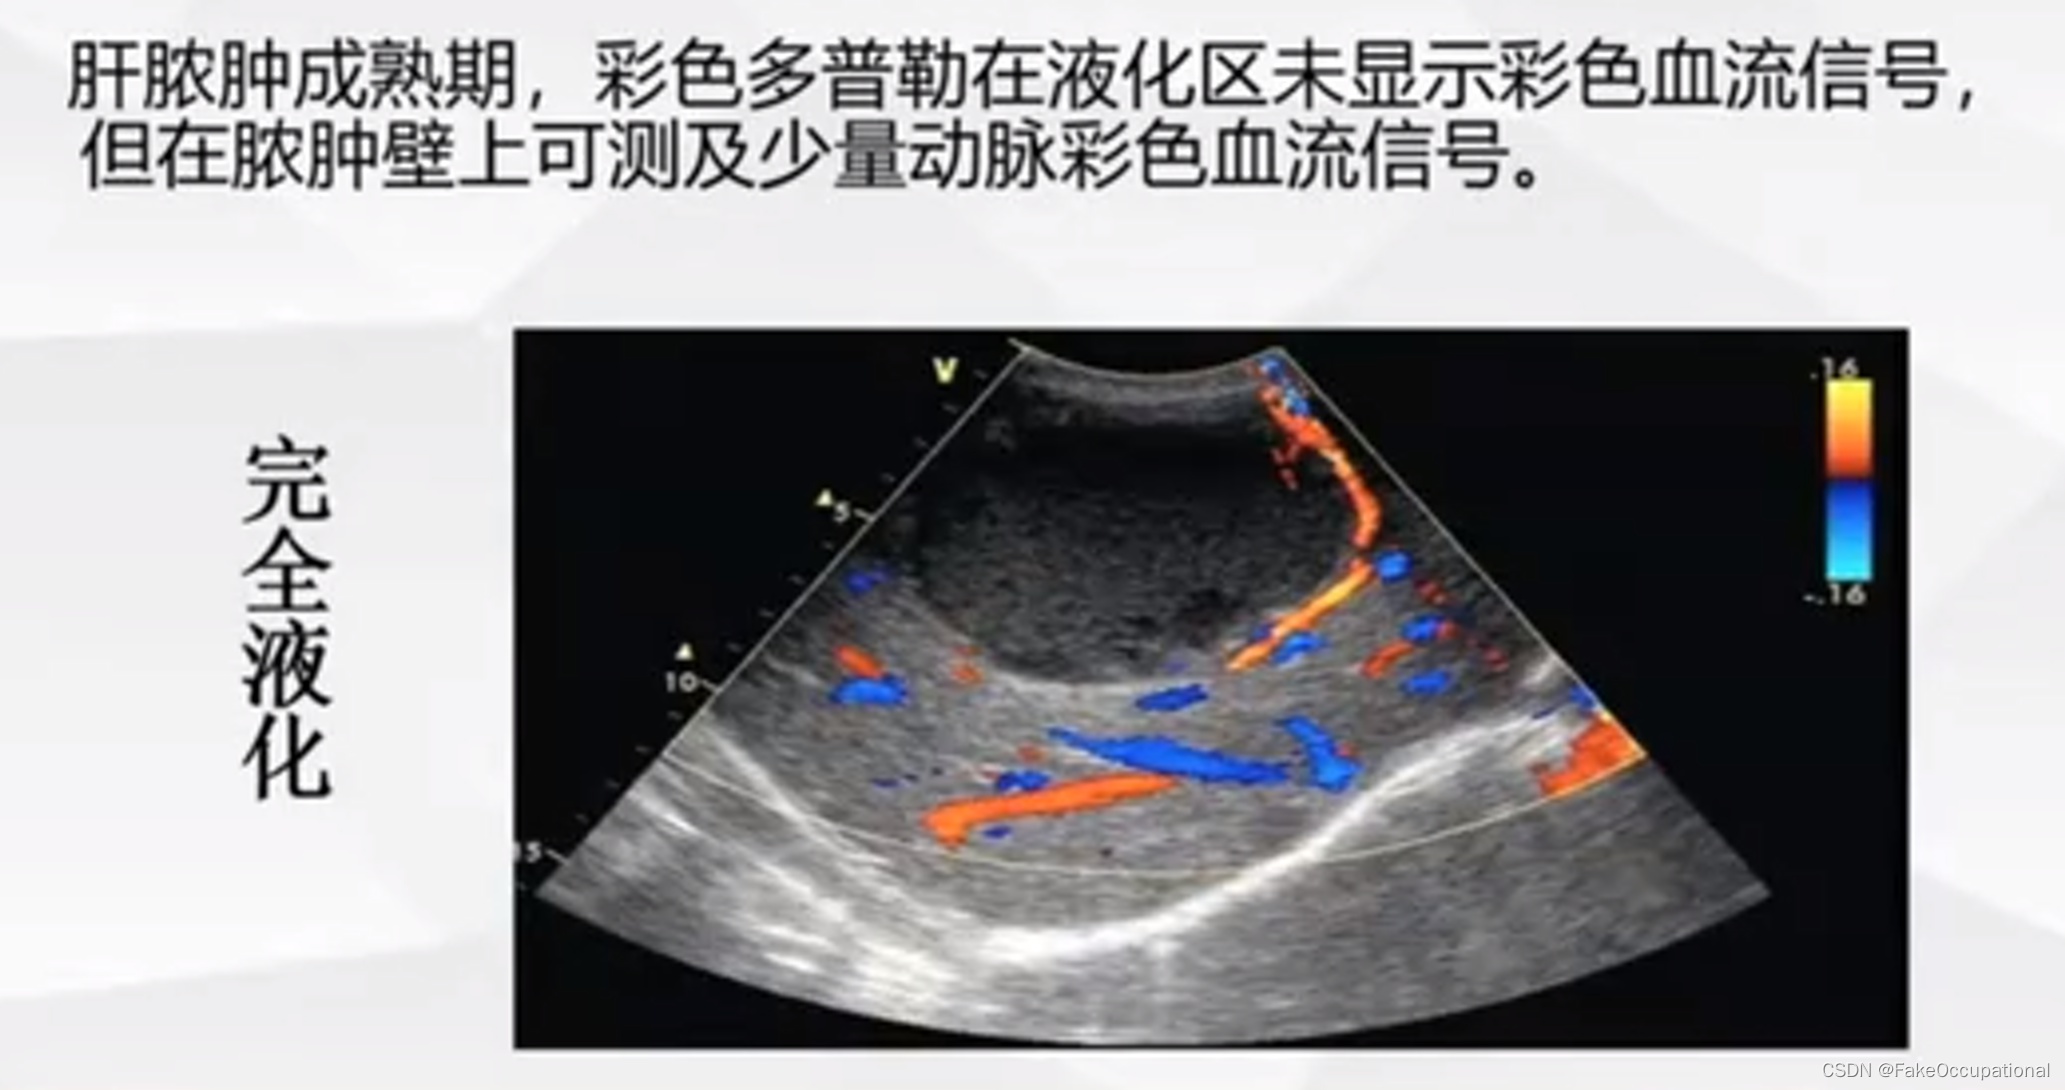

异常肝脏超声表现